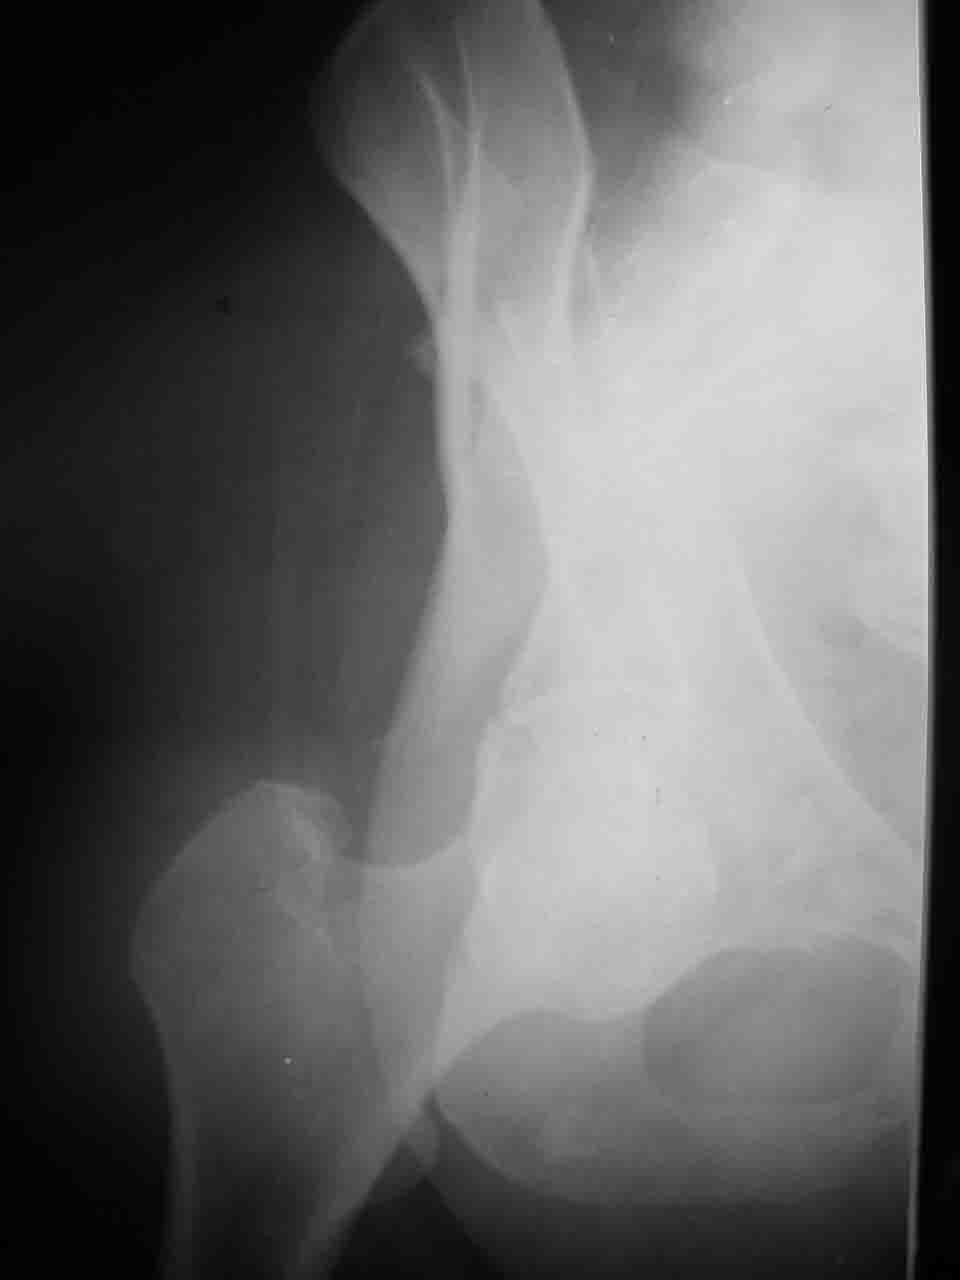

Re: Перелом вертлужной впадины

Спасибо за комментарии и рекомендации. Откровенно говоря, больного я прооперировал на прошлой неделе, через 5 дней после аварии и проблем с ним пока никаких нет, на удивление при достаточно обширной диссекции (илиофеморальный доступ) болей практически нет, так что больной самостоятельно садится в кровати, выполняет активные движения в оперированном суставе, сгибая до 60 градусов пока, далее с ассистенцией.

Причиной обращения к сообществу были возникшие непосредственно после операции сомнения и разочарования полученным качеством репозиции: а надо ли было трогать перелом вообще, репозиция передней колонны технически была очень сложна для меня, хотя реконструкции была в той же последовательности, что Д-р А.В.Рунков рекомендовал, в какой-то момент безуспешных манипуляций стал думать о *вторичной конгруэнтности*, которую не так давно обсуждали на

форуме и скелетном вытяжении. С репозицией и фиксацией задней колонны и отдельно задне-верхней стенки впадины проблем не возникло. Послеоп. Рг граммы в приложении. Если возникнут какие-либо дополнения или поправки - был бы признателен.